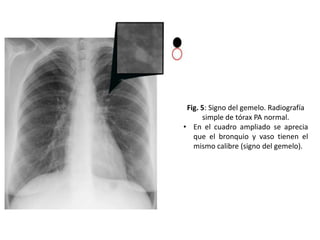

Fig. 5: Signo del gemelo. Radiografía

simple de tórax PA normal.

• En el cuadro ampliado se aprecia

que el bronquio y vaso tienen el

mismo calibre (signo del gemelo).